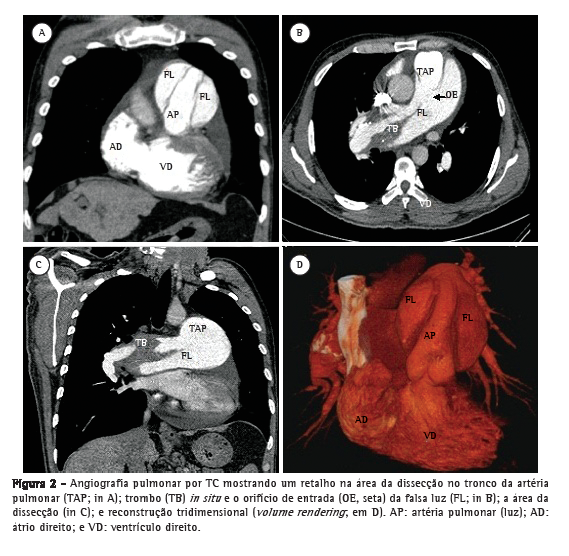

Paciente do sexo masculino, 50 anos, diagnosticado há quatro anos com hipertensão pulmonar relacionada à esquistossomose mansoni, admitido na emergência do Hospital das Clínicas da Faculdade de Medicina da Universidade Federal de Minas Gerais, localizado em Belo Horizonte, Brasil. Apresentava dor torácica retroesternal de início recente com agravamento progressivo e falta de ar (hipertensão pulmonar classe funcional III, de acordo com a Organização Mundial de Saúde). Havia sido diagnosticado com leucemia mieloide crônica há sete meses e estava em quimioterapia desde então. No momento da internação, o ecocardiograma transtorácico mostrava um grande trombo central não obstrutivo na artéria pulmonar principal direita. O átrio direito estava dilatado, e havia regurgitação tricúspide leve, com pressão sistólica em artéria pulmonar estimada em 63 mmHg. Foi diagnosticado como portador de trombose in situ como complicação de hipertensão pulmonar de longa duração. Após a possibilidade de síndrome coronária aguda ter sido excluída, recebeu alta em uso de varfarina. Foi reinternado dois meses depois em razão de dor torácica refratária com agravamento progressivo. Na época, apresentava SpO2 de 96%, e uma terceira bulha era audível no espaço paraesternal esquerdo inferior, acompanhada por murmúrio de regurgitação tricúspide. Os pulmões estavam limpos, e os pulsos arteriais periféricos estavam simétricos. Os exames laboratoriais estavam normais, incluindo os níveis séricos de creatinoquinase, creatinoquinase isoenzima MB e troponina. O eletrocardiograma de repouso evidenciava isquemia miocárdica aguda nas derivações anteriores. O ecocardiograma Doppler transtorácico revelava pressão sistólica da artéria pulmonar de 62 mmHg, um trombo na artéria pulmonar direita, como no exame anterior, e a presença de um retalho naquele nível que era compatível com dissecção da artéria pulmonar (Figura 1). O diagnóstico foi subsequentemente confirmado por angiografia pulmonar por TC (APTC; Figura 2). O paciente foi transferido para outro centro de tratamento cardiovascular, onde foram realizadas tentativas de correção do defeito por meio de um procedimento endovascular (através da veia femoral). No período perioperatório, o paciente apresentou choque cardiogênico refratário. Todos os esforços para reanimar o paciente foram infrutíferos, e ele faleceu na sala de cirurgia.

Até onde sabemos, este é apenas o segundo relato de um caso de dissecção da artéria pulmonar em paciente com hipertensão pulmonar relacionada à esquistossomose, sendo que o primeiro caso foi diagnosticado em autópsia.(6) Clinicamente, esses casos apresentam agravamento de sintomas anteriores de dispneia e dor torácica. A dor torácica é normalmente acentuada e pode simular síndrome coronariana aguda ou dissecção aguda da aorta. Cianose pode estar presente.(7) O diagnóstico é muitas vezes obtido post mortem, pois a maioria dos pacientes morre subitamente em razão de tamponamento cardíaco ou sangramento pulmonar grave. Se o diagnóstico é feito ante mortem, o primeiro achado é a emergência de um retalho na luz da artéria ou tronco pulmonar dilatado que se forma a partir da camada da íntima, denotando o orifício de entrada da falsa luz, mas raramente uma saída, que é o oposto do que é encontrado em casos de dissecção aórtica.(8) A ressonância magnética ou a APTC de tórax podem confirmar o diagnóstico e as complicações associadas, como aumento da dilatação da artéria pulmonar, sangue no líquido pleural e opacidades pulmonares.(1) A evolução é geralmente a ruptura do vaso com sangue se espalhando para o mediastino, pericárdio ou pulmão, pois não há saída da falsa luz. O orifício intimal que leva à dissecção ocorre no ponto de maior dilatação como consequência de um aumento da tensão parietal. Há relatos de que a inflamação causada por trombose in situ pode desempenhar um papel sinérgico no desenvolvimento da ruptura intimal.(4,9,10)